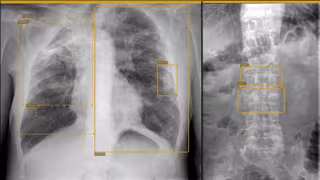

Archivo - Radiografía de columna vertebral

Archivo - Radiografía de columna vertebral - HOSPITAL DE LA CANDELARIA - Archivo